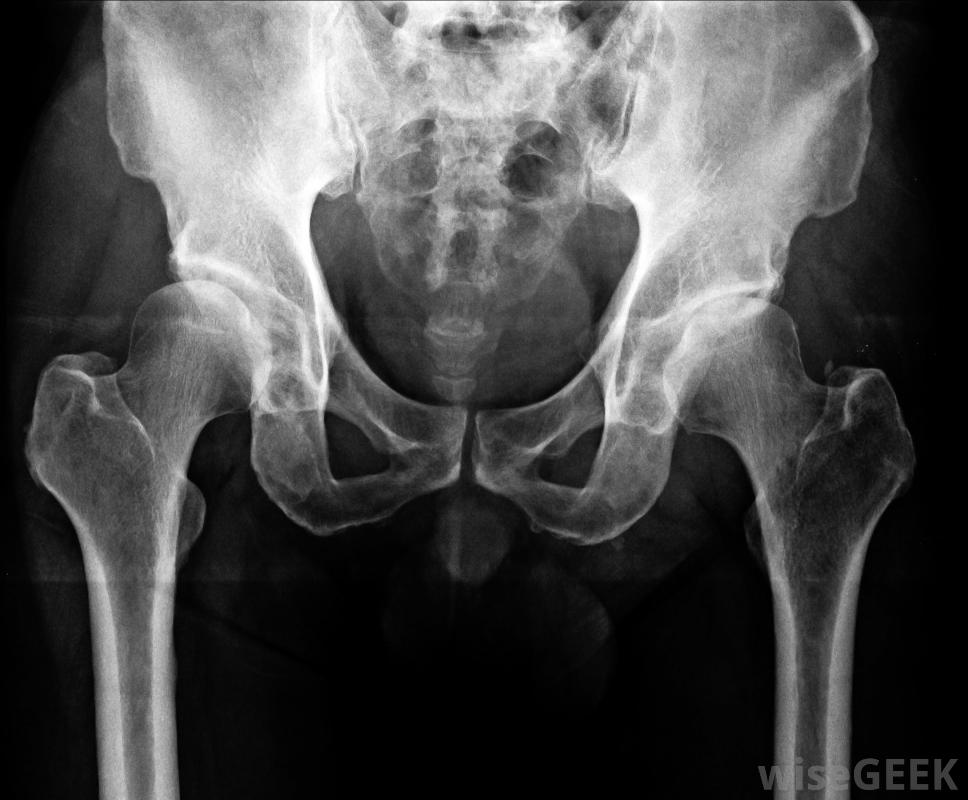

在实际注射之前,在局部麻醉前用碘和酒精混合物清洗髋关节,在透视或活体X光和对比染料的引导下,将小针插入关节区,用于避免神经损伤并确保针头到达预期的关节区域。将集中剂量的消炎药输送到患处并拔出针头。

X光可用于帮助髋关节注射。

在髋关节注射前,应将一根小针插入关节区域在X光的指引下。